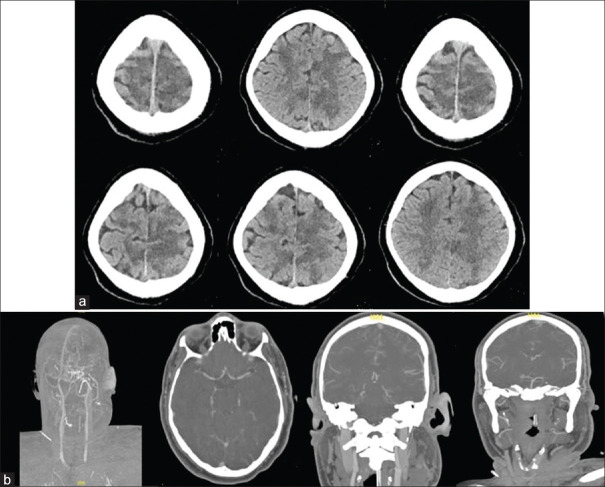

Posterior reversible encephalopathy syndrome (PRES) is a neuroradiological syndrome, clinically present by impaired consciousness, headache, visual disturbances, and seizures, and radiologically brain edema. Cases of PRES induced by blood transfusion are rarely documented. We report this case to increase the awareness of treating physicians for the possible complications of rapid blood transfusion. A 29-year-old man presented with polytrauma and was in hemorrhagic shock. He was transfused with multiple transfusions. Later, he was found to have quadriplegia with minimal movement of fingers in the left hand. His computed tomography showed cerebral edema in multiple cerebral regions. We propose that the etiology in this case is that rapid blood transfusion induced acute rise in hemoglobin which led to PRES. The influences of blood transfusion on blood flow, blood viscosity, and endothelial dysfunction lead to blood-brain barrier dysfunction, which can result in PRES.

后可逆性脑病综合征(PRES)是一种神经放射综合征,临床表现为意识障碍、头痛、视力障碍和癫痫发作,影像学表现为脑水肿。输血诱发 PRES 的病例很少见。我们报告此病例是为了提高主治医生对快速输血可能引起的并发症的认识。一名 29 岁的男子因多发性创伤而出现失血性休克。他接受了多次输血。后来,他被发现四肢瘫痪,左手手指活动微弱。他的计算机断层扫描显示多个脑区出现脑水肿。我们认为本病例的病因是快速输血引起血红蛋白急剧升高,从而导致 PRES。输血对血流量、血液粘度和内皮功能障碍的影响导致血脑屏障功能障碍,从而引发 PRES。